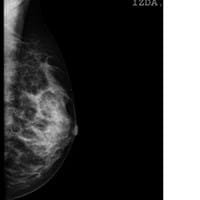

Interpretación mamografía bilateral mamaria

Buenas tardes, me han diagnosticado una asimetría de la densidad nodular, no bien delimitada en CSE de la mama izquierda de 3cm. Tres días antes, mi ginecólogo me mandó la mamografía porque en la eco se veía algo de un tamaño como la tapita de arriba...

Interpretar fibroadenoma o cáncer en mamografía

¿Cómo puedo diferenciar en una mamografía un fibroadenoma de algo maligno?

¿Es un fibroadenoma?

Buenos días, ¿Me pueden decir de qué tiene pinta esta mamografía? Me han dicho que se ve algo. Mi ginecólogo me dijo que se veía algo de medio cm muy pequeño y en la mamografía me ponen que es de 3 cm. ¿Alguien me puede ayudar? Podéis mojaros, no me...